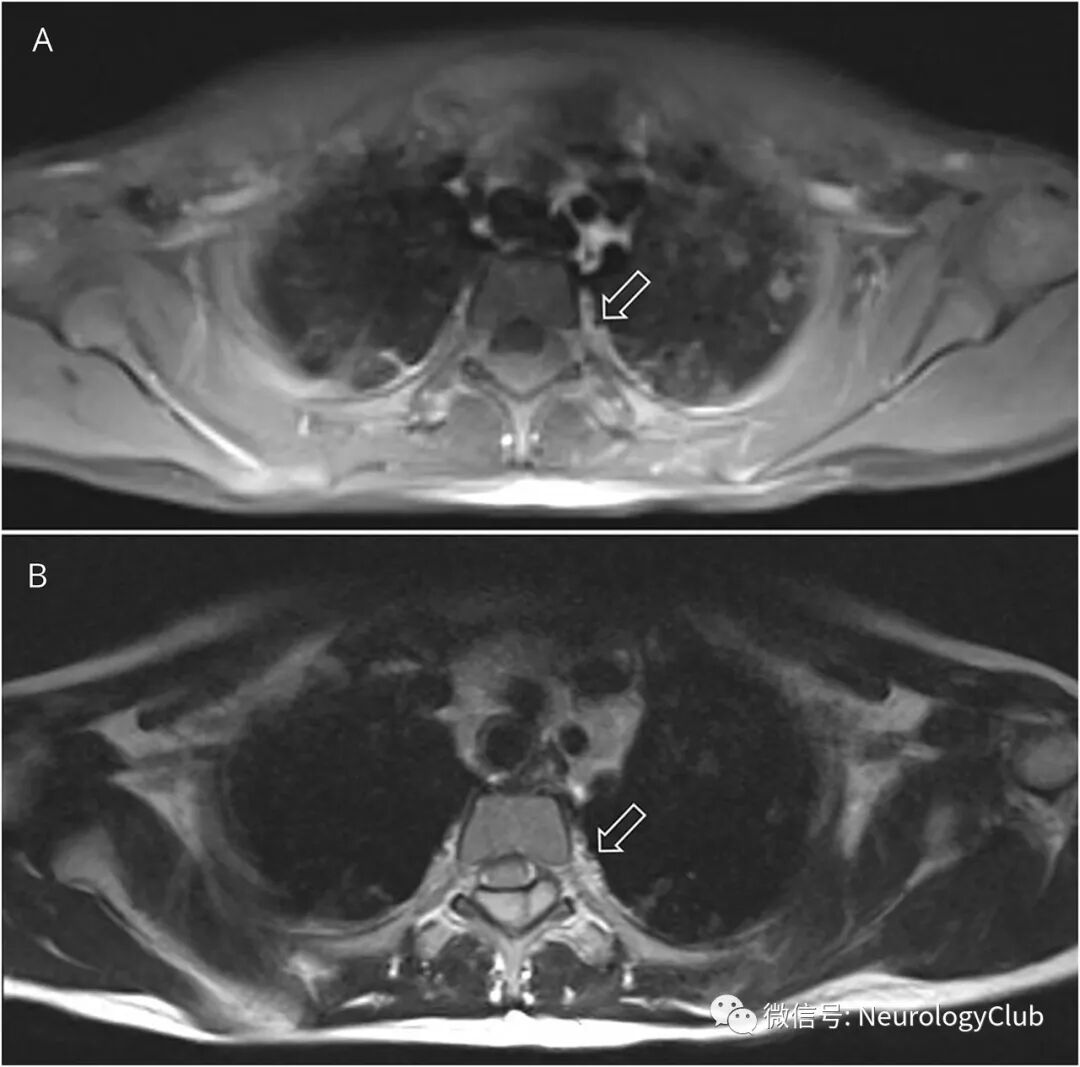

7岁女孩,表现为双腿进行性无力和感觉异常1周。脊髓矢状位MRI可见T3-T8水平一大的硬膜外血肿伴病灶内分隔(图1)。横断面上,病灶从左侧椎间孔延伸至椎旁区域,并与增厚的左侧胸膜融合(图2)。MRI可见多发肺内结节。

(图2:A:T1WI;B:T2WI;MRI提示高信号背侧肿块;从左侧椎间孔延伸至椎旁区域,并与增厚的胸膜融合[白箭];可见多发肺内结节)